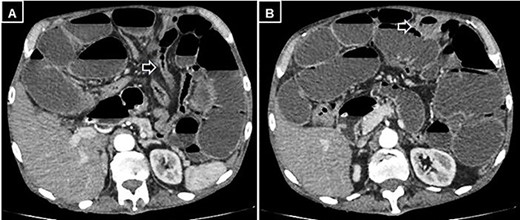

A supine and upright plain X-ray of the abdomen were obtained and showed dilated small bowel loops, mainly in the left upper abdomen, along with multiple air-fluid levels (Fig. 1). Computed tomography (CT) demonstrated significant air-fluid distention of the entire small bowel, up to the right flank and periumbilical region, where a change in caliber was observed (Fig. 2). The findings corresponded to small bowel obstruction (Fig. 3).

Abdominal and pelvic CT with intravenous contrast. Coronal image illustrating dilated fluid-filled loops of the small intestine consistent with high-grade mechanical obstruction.